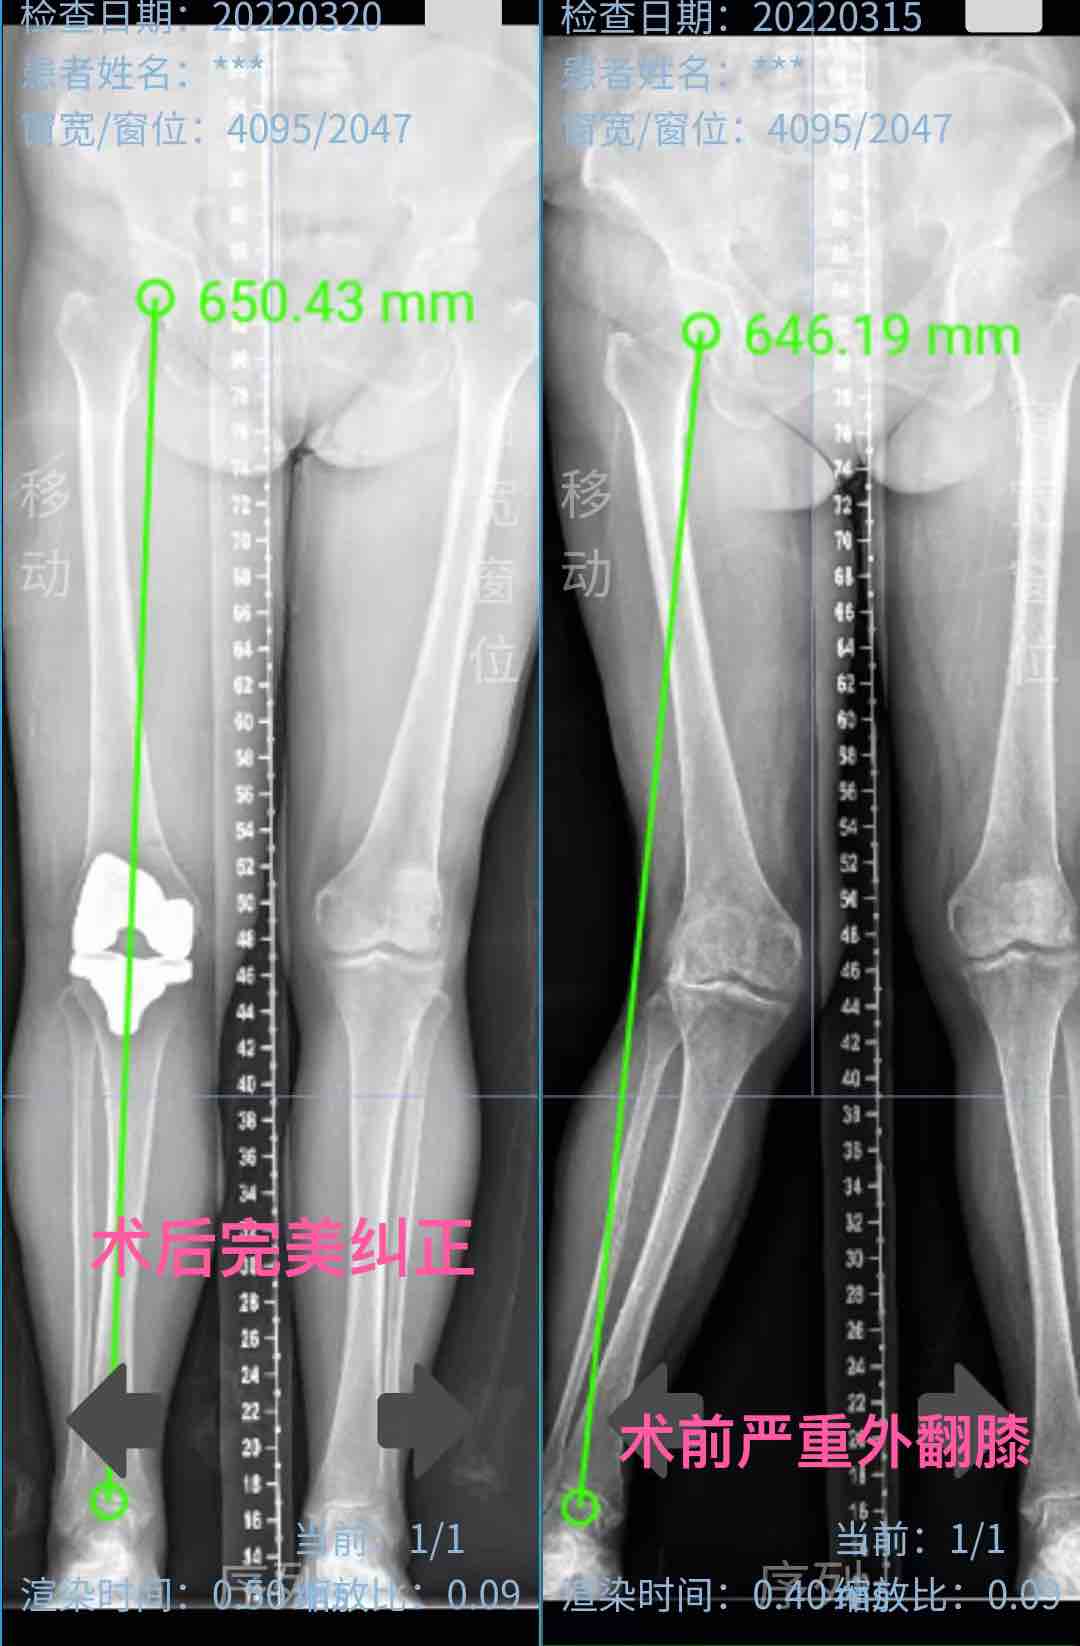

另一个是严重的外翻膝,平时人工手术都会做大量的软组织松解,而机器人做先平衡软组织再调整截骨方案最后完成截骨后,软组织基本完全平衡,不需要大量松解而达到了一个很完好的手术结果。这样就达到了精准化个性化的完美关节置换。